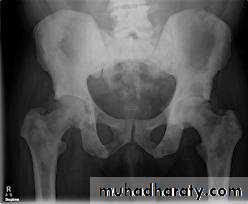

Plain film:-

* Enlargement of bladder shadow due to residual urine.

*Prostatic calculi or calcification .

Produce similar changes except:

* Plain film shows evidence of metastasis to the bone especially in the pelvis .* The prostatic urethra shows irregular narrowing and stretching .

* US can distinguish between BPH & Ca.